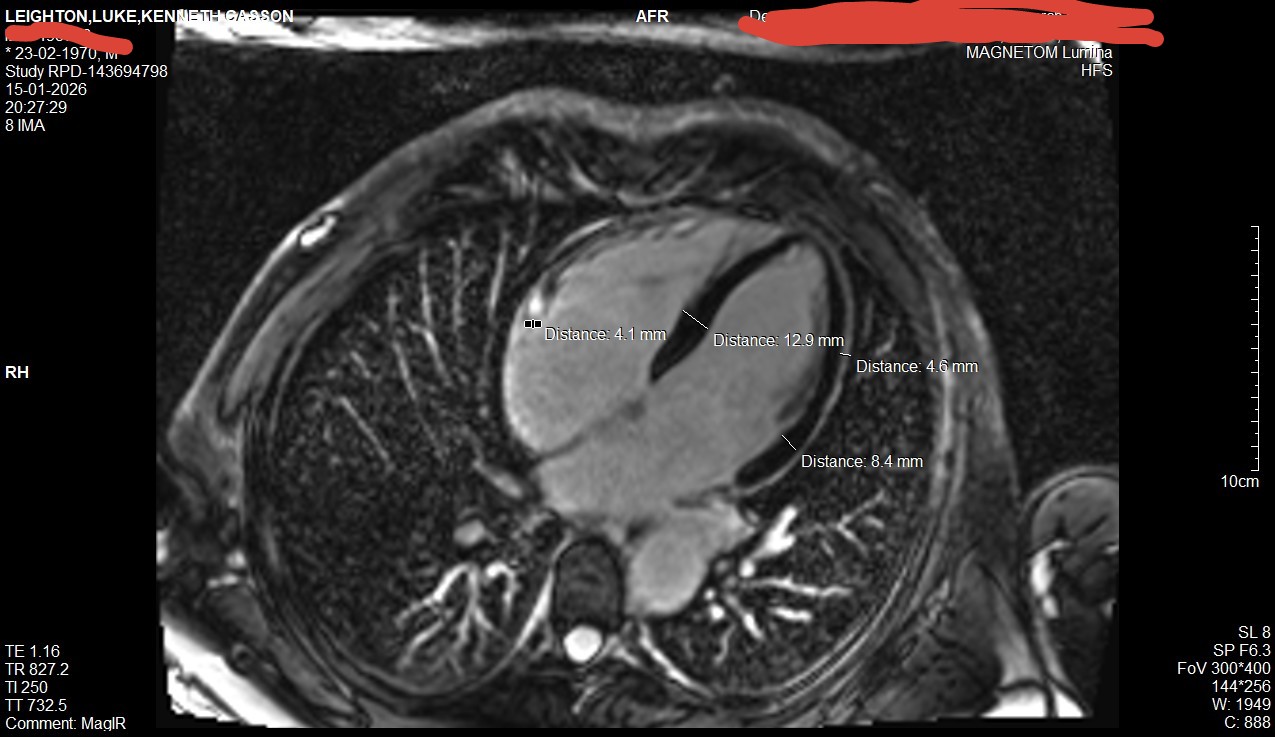

I have been examining the Cardiac MRI every

day, and researching symptoms.

firstly: the pericardium (sac around the heart) is

4.6 mm in places, indicating severe infection.

the normal width is below 2mm (0.8 +/- 1.2)

second: the left ventricle is on the border of "mild"

hypertrophy, at 12.9mm in the middle (actually

I missed part of the black muscle area, it is slightly

more) and 8.4mm at the edge (again

under-measured). also although it is unclear and I

had not measured it before, the right ventricle is

an estimated 5-6 mm where the normal range

is 3-4 mm

thirdly: there is a 4.1 mm diameter white spot on

the right, which if I pan through the slices is

present on several, likely indicating a calcified

blood vessel or other anomalous artefacts.

fourthly: on the right side of the heart (just below

the 4.1 mm marker) is some white stuff. again this

should not be there: it is not present on "normal"

cardiac MRI scans.